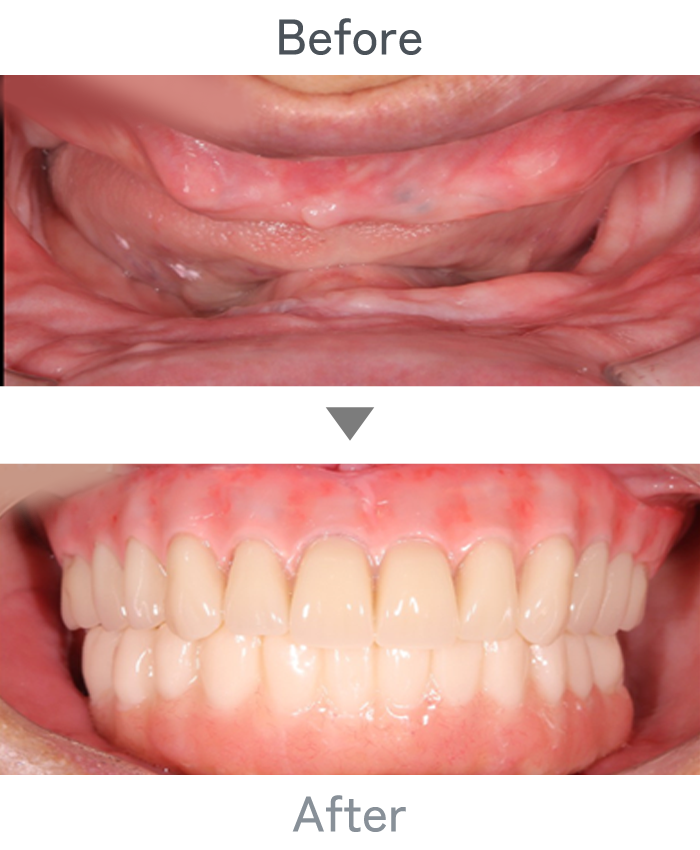

All-on-4

+

金属床義歯

主訴 入れ歯が使えなくて固定式にしたい

治療法 上顎:金属床義歯

下顎:All-on-4

治療期間 4ヶ月

※仮歯は手術当日に装着

費用 ・上顎金属床義歯:200,000円

・下顎All-on-4:2,500,000円

小 計:2,700,000円

消費税:270,000円

合 計:2,970,000円

※インプラント体、上部構造ともに『10年保証』

副作用

• メンテナンスが必要